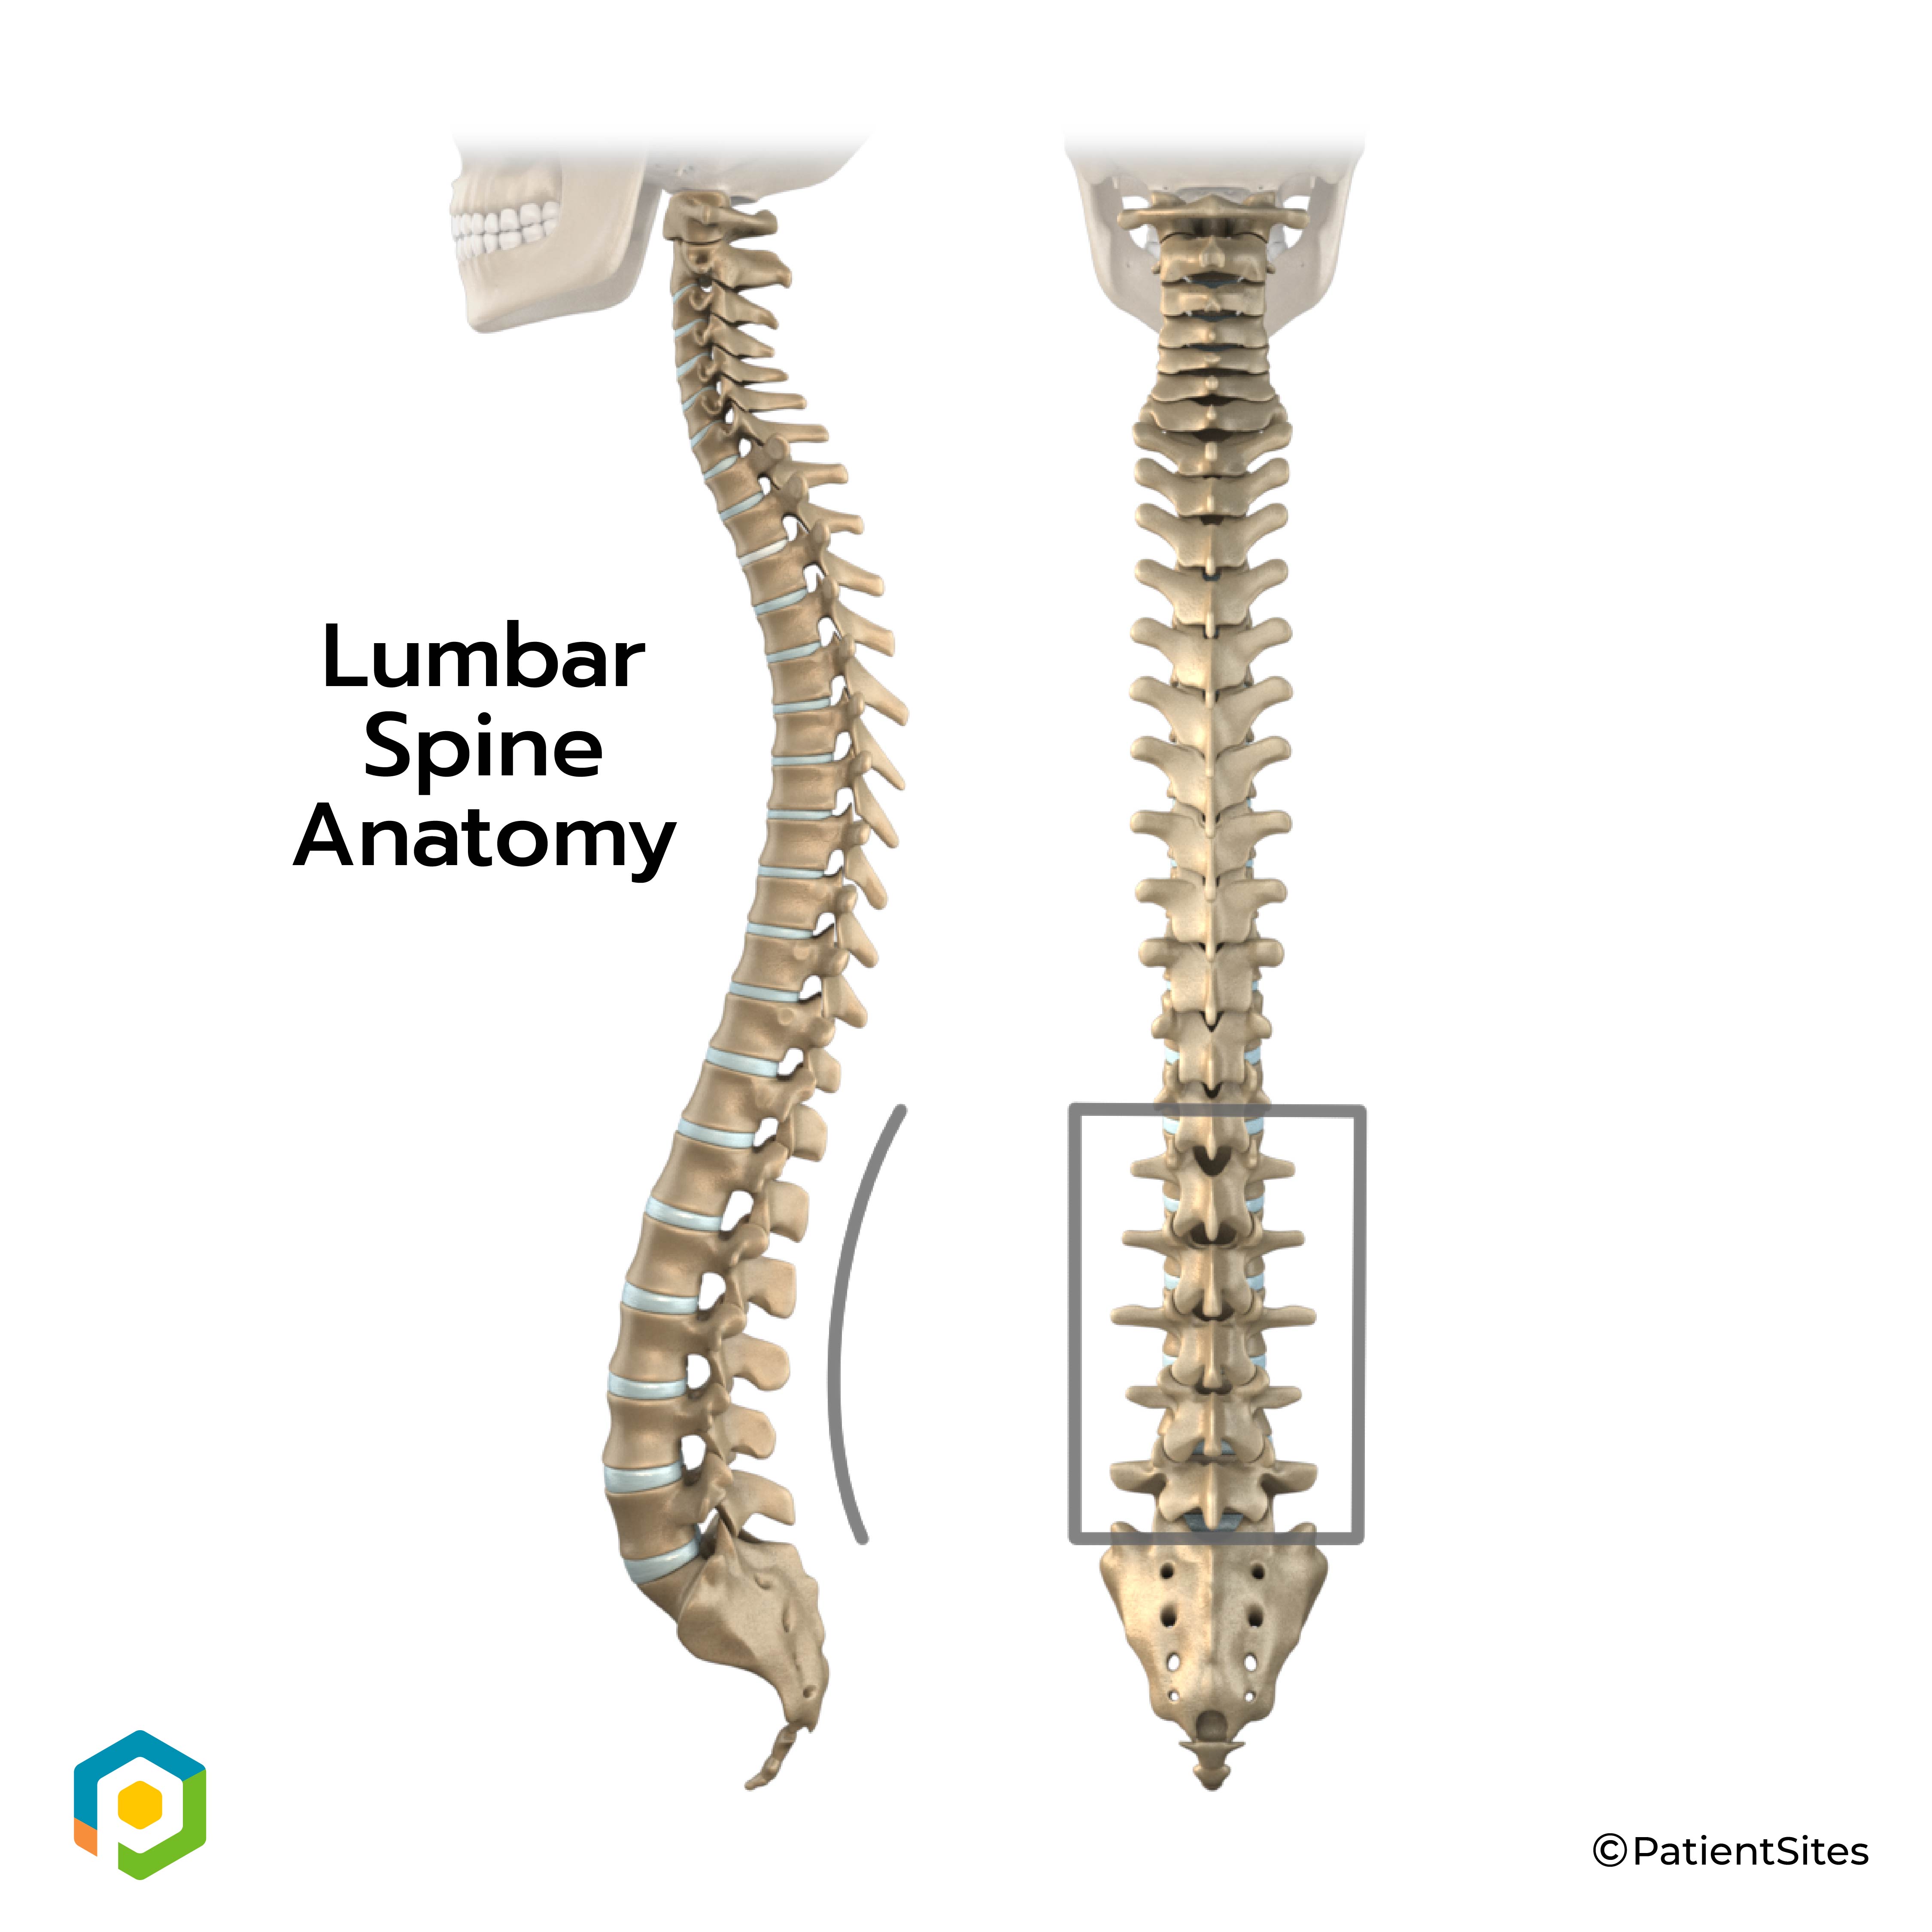

Anatomy

What part of the back is involved?

The human spine is made up of 24 spinal bones, called vertebrae. Vertebrae are stacked on top of one another to create the spinal column. The spinal column gives the body its form. It is the body's main upright support.

Human Spine

The back portion of the spinal column forms a bony ring. When the vertebrae are stacked on top of each other, these bony rings create a hollow tube. This tube, called the spinal canal, surrounds the spinal cord as it passes through the spine. Just as the skull protects the brain, the bones of the spinal column protect the spinal cord.

Related Document: FYZICAL San Francisco's Guide to Lumbar Spine Anatomy